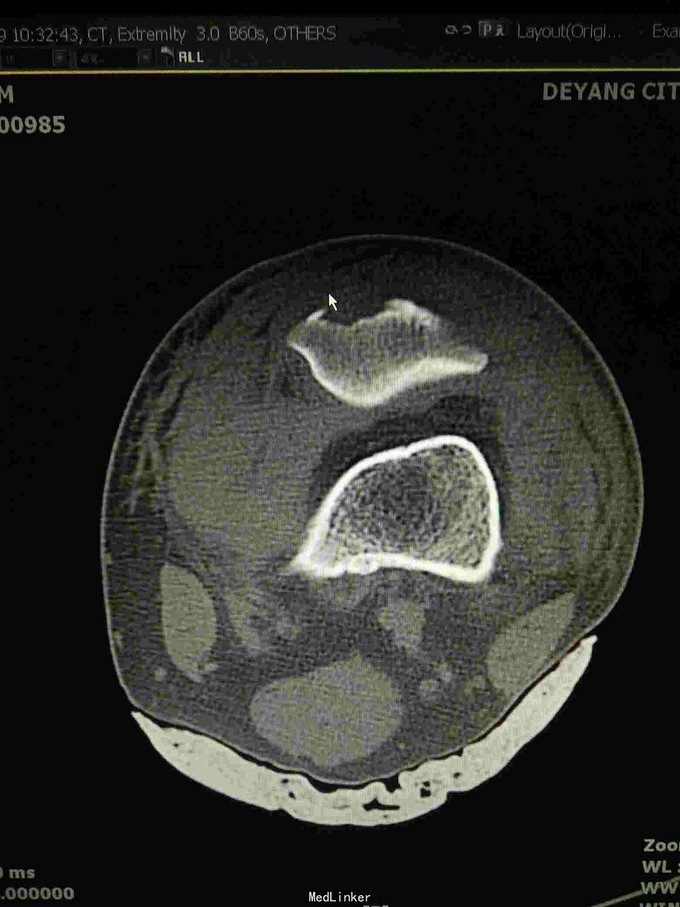

左髌骨粉碎性骨折

查体:左下肢活动受限,背伸障碍,左膝关节明显肿胀,压痛,扪及骨擦感,左足感觉及血循环可。 x片:左髌骨骨折。

诊断:左髌骨粉碎性骨折; 治疗,石膏固定,消肿止痛,行髌骨骨折切开复位克氏针内固定术,术中克氏针张力带钢丝固定,术后石膏固定。